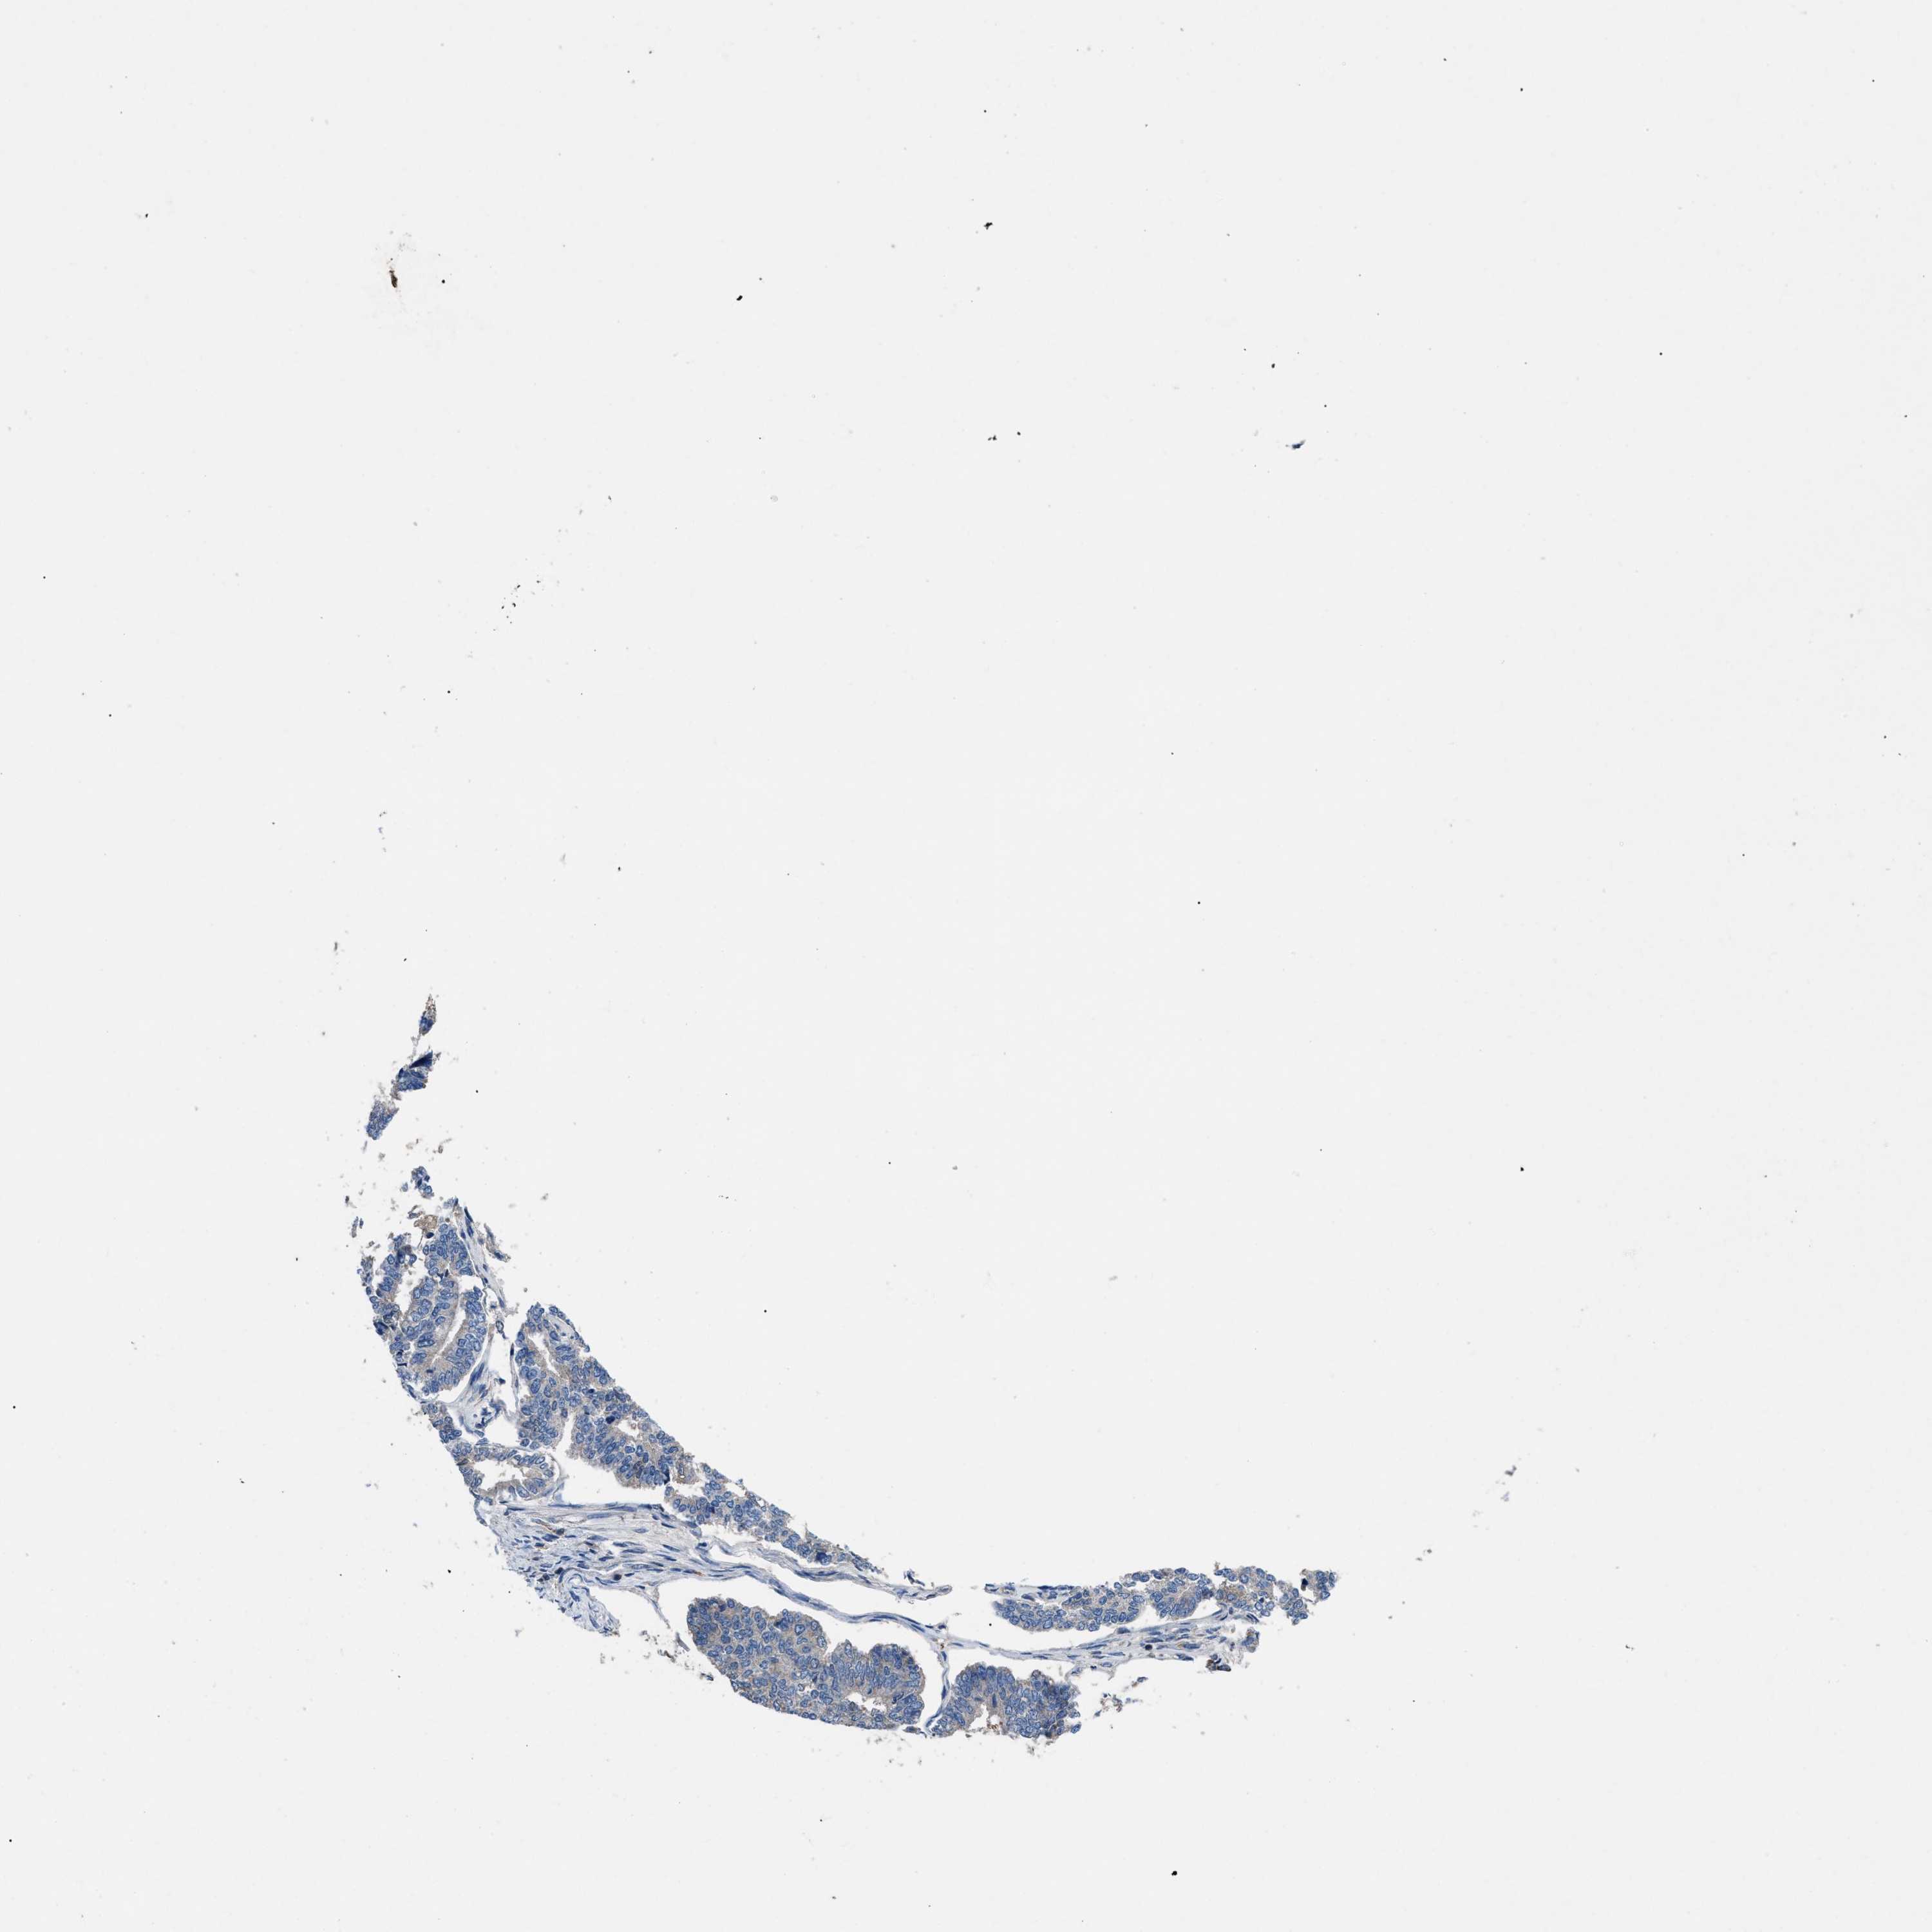

ENDOMETRIAL CANCER - Protein expressioni

A mouse-over function shows sample information and annotation data. Click on an image to view it in a full screen mode. Samples can be filtered based on level of antibody staining by selecting one or several of the following categories: high, medium, low and not detected. The assay and annotation is described here.

Note that samples used for immunohistochemistry by the Human Protein Atlas do not correspond to samples in the TCGA dataset.

Antibody stainingi

Antibody staining in the annotated cell types in the current human tissue is reported as not detected, low, medium, or high, based on conventional immunohistochemistry profiling in selected tissues. This score is based on the combination of the staining intensity and fraction of stained cells.

Each image is clickable and will lead to virtual microscopy that enables deeper exploration of all samples and also displays staining intensity scores, fraction scores and subcellular localization as well as patient and tissue information for each sample.

Antibody HPA018162

Staining

High

Medium

Low

Not detected

Intensity

Strong

Moderate

Weak

Negative

Quantity

>75%

75%-25%

<25%

None

Location

Nuclear

Cytoplasmic/membranous

Cytoplasmic/membranous,nuclear

Adenocarcinoma, NOS